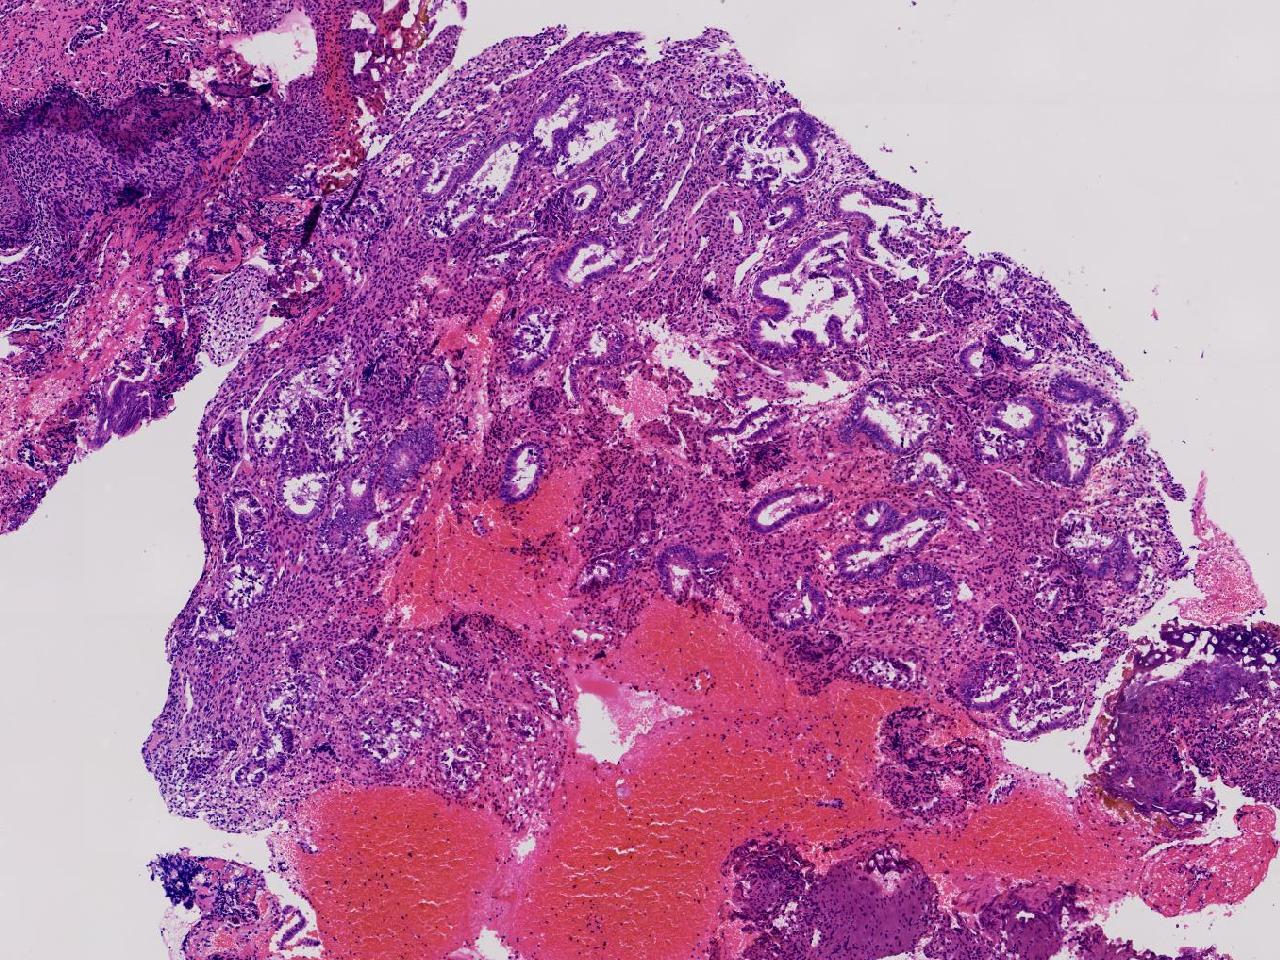

性别

女

年龄

55岁

女,55岁,月经紊乱4年,彩超示:子宫内膜增厚(内膜厚15.7mm),末次月经:2025年7月27日。

标本名称

宫腔镜下子宫内膜活检

大体所见

灰粉色不整形软组织多块,1.5X0.8X0.6厘米。

考虑:子宫内膜增生伴子宫内膜炎

子宫内膜增生紊乱,内膜息肉样结构